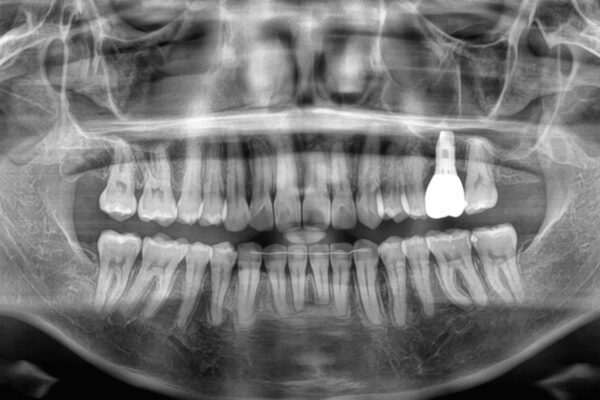

挺出歯を圧下してスペースを確保!目立たない部分矯正で下顎大臼歯にインプラント治療を実現

挺出歯を圧下してスペースを確保!目立たない部分矯正で下顎大臼歯にインプラント治療を実現 ビフォー 挺出歯を圧下してスペースを確保!目立たない部分矯正で下顎大臼歯にインプラント治療を実現 アフター

「1年前に抜歯した右下の奥歯にインプラントを入れたい」とのことで来院されました。